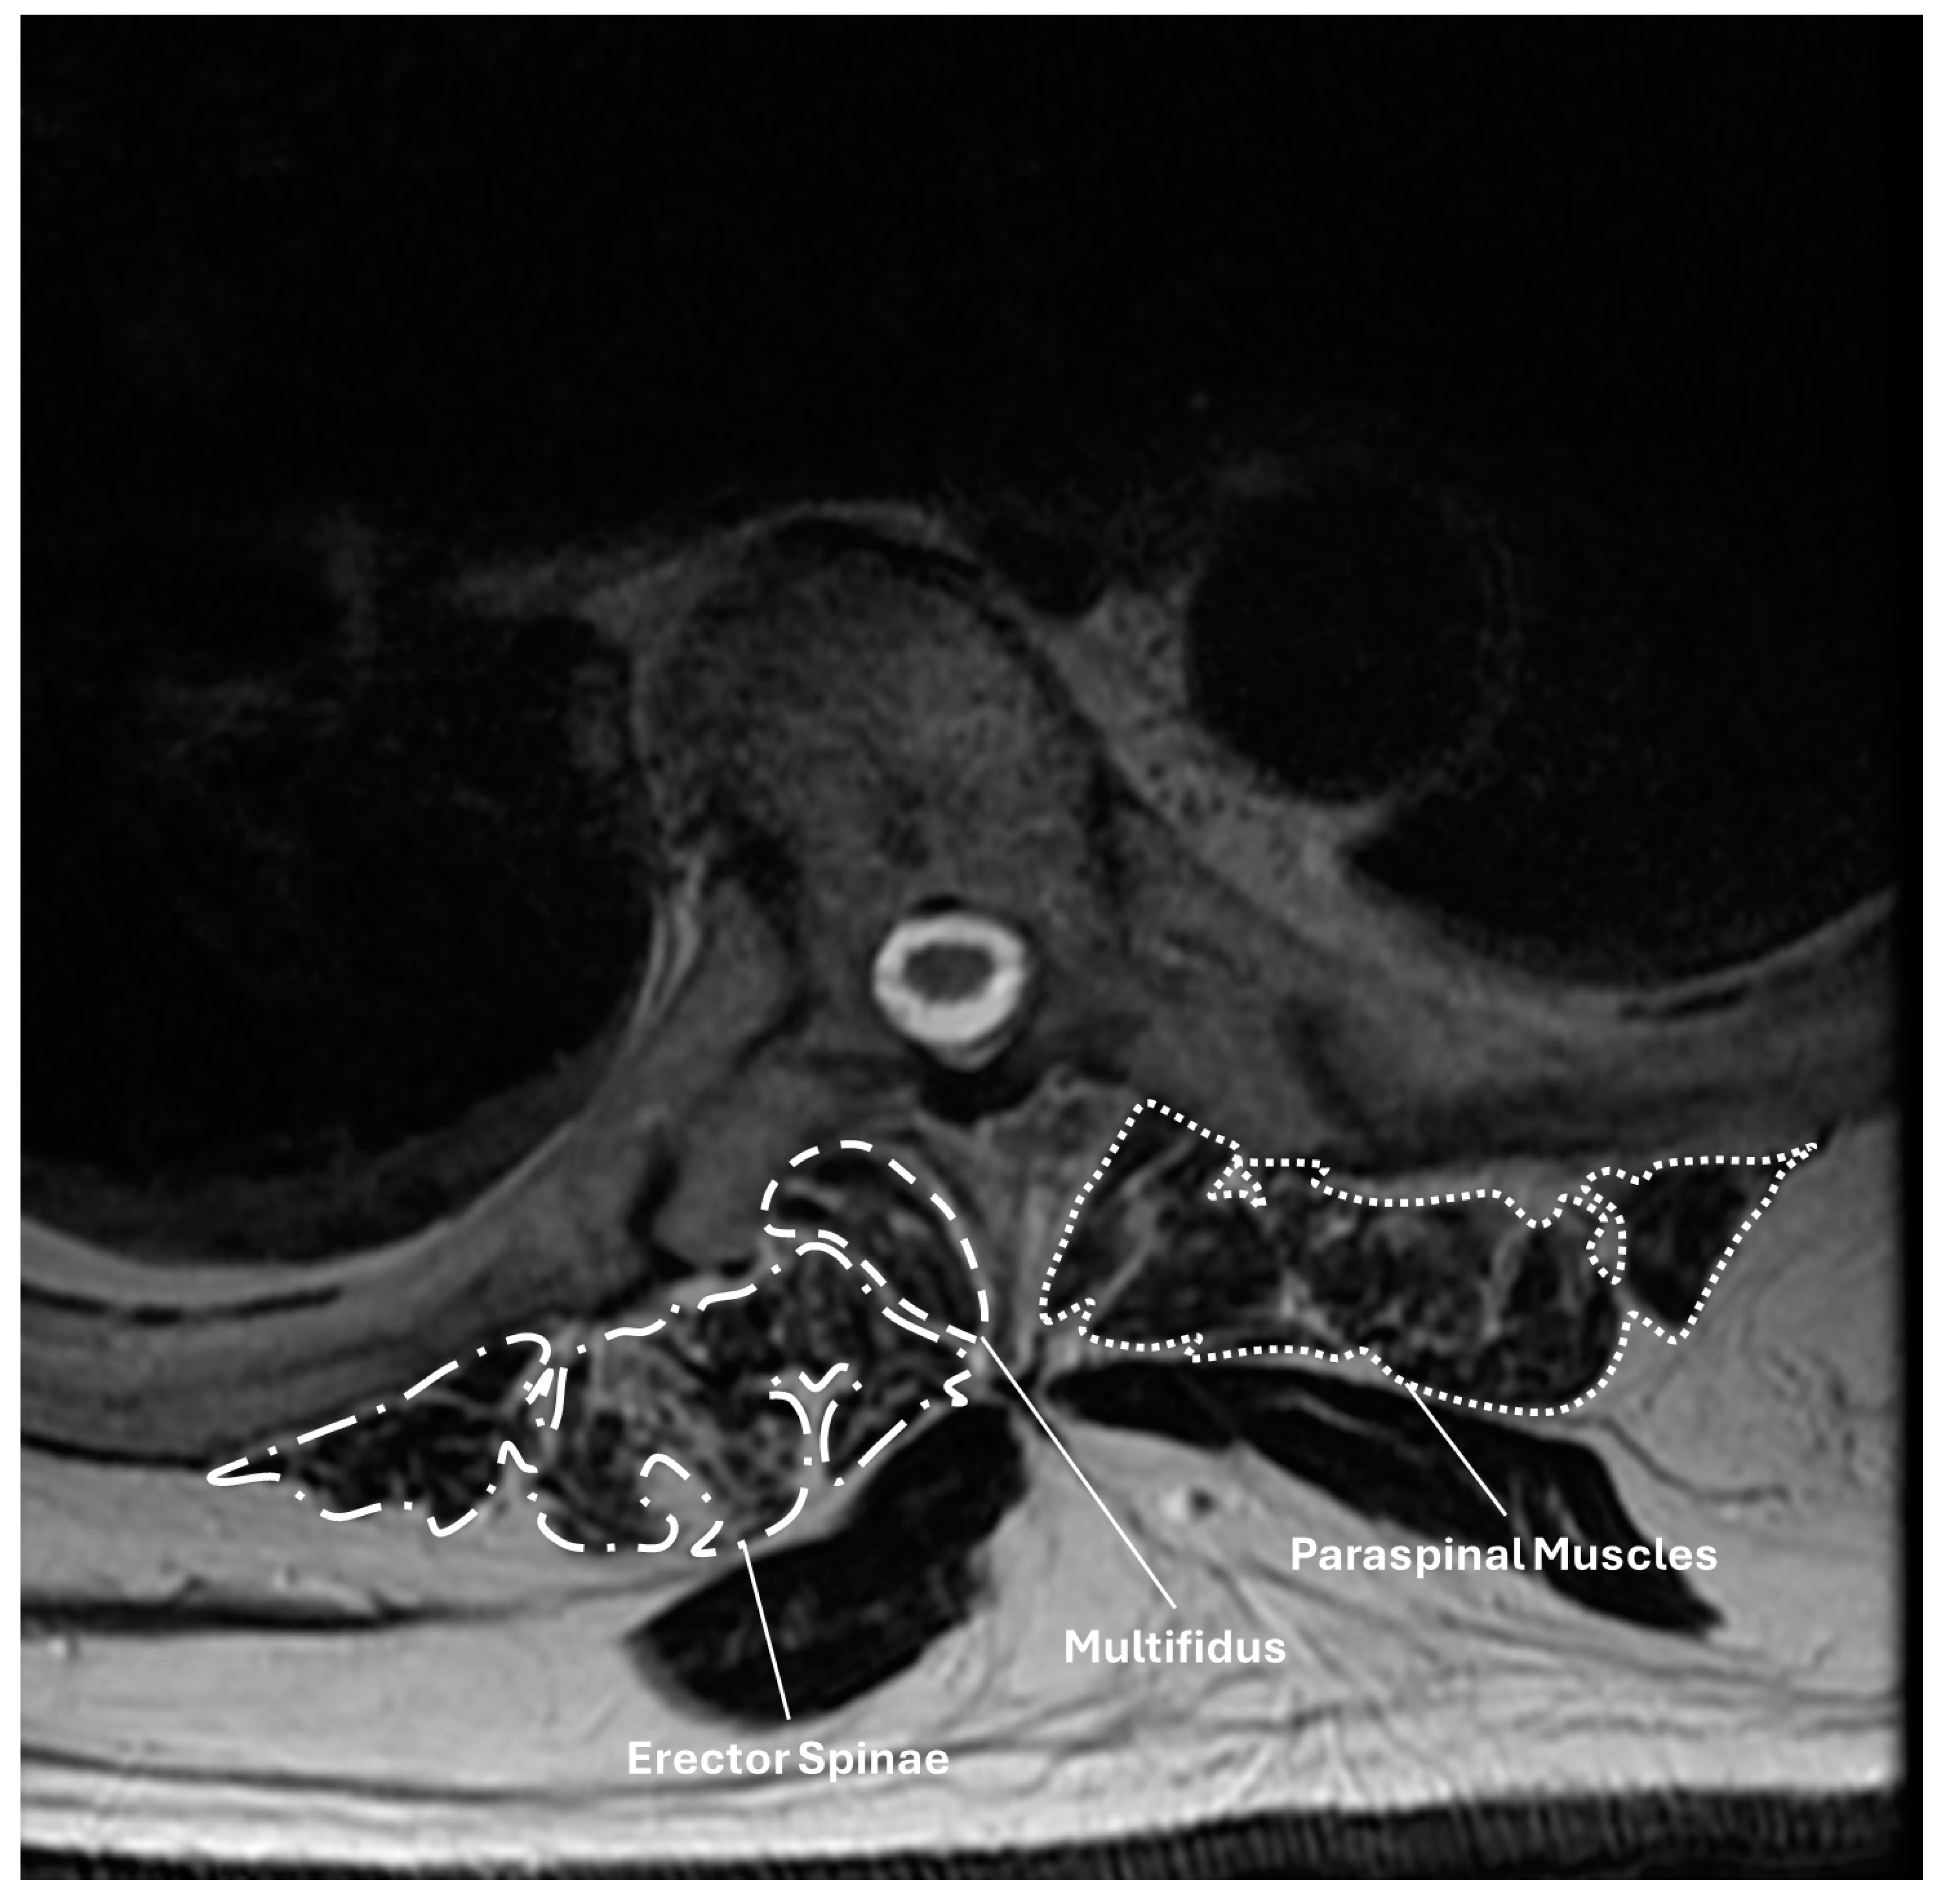

2. Materials and Methods